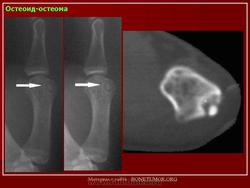

Рентгенологическая картина остеоид-остеомы весьма характерна. Рентгенологические симптомы возникают значительно позже клинических проявлений опухоли, и первым на рентгенограмме обнаруживают склероз кости. На участке поражения формируется одностороннее или муфтообразное утолщение кости в виде гиперостоза. Позднее в толще гиперостоза формируется основной отличительный признак остеоид-остеомы - ее «гнездо» в виде очага разрежения диаметром до 1 см, внутри которого могут отмечаться мелкие костные включения. Сквозь слой склерозированной ткани «гнездо» опухоли на обычных рентгенограммах не всегда дифференцируется и для ее выявления применяют лучи повышенной жесткости и томографию. Обнаружение «гнезда» необходимо для подтверждения диагноза и проведения направленного оперативного вмешательства.